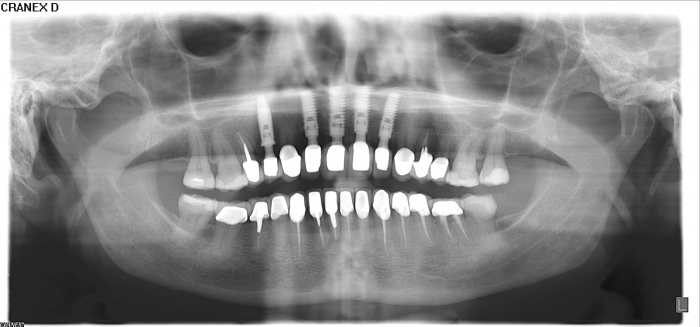

Rx Panorâmico final 2019